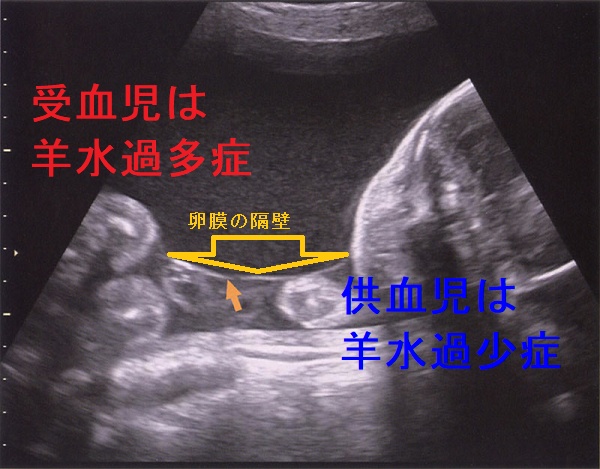

双胎間輸血症候群(そうたいかんゆけつしょうこうぐん:Twin-to-twin transfusion syndrome:TTTS)は、一卵性双胎児が1つの胎盤を共有し(1胎盤2羊膜、1絨毛2羊膜)、栄養血管が一部つながっている(吻合血管)ためにおこります。胎児への血液供給は不均等になり、胎盤血流が多い児と少ない児に分かれ異常な発育を来します。

血液を多くもらう児(受血児)は、循環血液量が増えて

- 腎血流量も増加→羊水過多症

- うっ血性心不全

血液が盗られ胎盤血流が少ない児(供血児)は、

- 発育不全・肺低形成

- 低血糖

- 腎血流量が減少→羊水過少症、腎不全起き

、どちらも正常な発育が望めません。

双胎間輸血症候群(TTTS)も妊娠時一過性甲状腺機能亢進症の原因となります。合併症のない双子妊娠と比較して、hCG値は有意に高く、妊娠時一過性甲状腺機能亢進症を起こしやすい[Eur J Obstet Gynecol Reprod Biol. 2009 Jun;144(2):124-9.]。